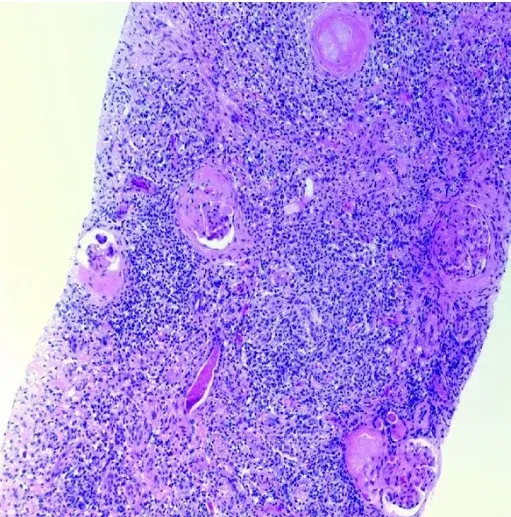

glomerulopatias

imagens